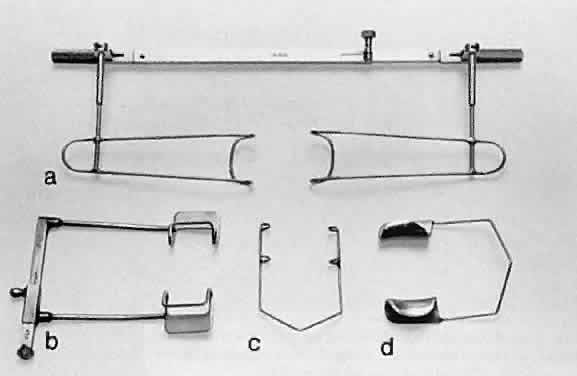

Toothed forceps can have teeth at a 90-degree angle (surgical forceps) or

angled teeth (mouse-tooth forceps; Fig. 17). An example of a surgical toothed forceps is a 0.12-mm forceps; an example

of a forceps with angled teeth is the O'Brien forceps. Microscopic

examination of the instrument from the side determines tooth design. A

toothed forceps is needed for tough tissue, such as the cornea or

sclera, whereas soft tissues, such as the iris or conjunctiva, are better

handled with a smooth forceps (see Fig. 16). Surgical toothed forceps may damage delicate tissue; however, these

forceps exert a high degree of resistance, which is necessary for manipulating

tougher tissues. Forceps with angled teeth can seize tissue lying

in front of the end of the blades. For example, these forceps can

be used to grasp the muscle insertion through the conjunctiva (Fig. 18). The forceps can grasp a minimal amount of tissue and produce minimal

surface deformation, frequently without penetrating the tissue. The angle-tooth

forceps can be useful for grasping the cornea during corneal

transplant surgery or repair of corneal lacerations. If the teeth are

dull or bent, the forceps become ineffective. The number and orientation

of the teeth on a forceps affect the stability of fixation and tissue

damage. Teeth angled at 90 degrees provide good fixation, but greater

tissue damage than teeth angled at 45 degrees (mouse-tooth forceps). Increasing

the number of teeth also increases the degree of tissue

fixation. One example is the Thorpe corneal fixation forceps, in which

the 90-degree teeth are in a 2 × 3 configuration. The Thorpe corneal

fixation forceps has been modified with 45-degree angled 0.12-mm

teeth in a 2 × 3 configuration, thus allowing for increased stability

of tissue fixation, with limited tissue damage. When driving or

passing a needle through tissue that is fixed with a toothed forceps, the

forceps should be held such that the needle enters the tissue on

the side of the forceps with the greatest number of teeth. In other words, when

a Thorpe corneal fixation forceps is used, the needle should

pass through the tissue on the edge that is secured by three teeth. This

maneuver limits the twisting of the tissue as the needle is advanced

through the tissue. Finally, an alternative is the Pierse-type forceps, which

has no teeth but has a small hollow area immediately posterior

to the tip. This hollow area allows for tissue displacement instead

of the tearing of tissue that occurs with sharp-toothed forceps.  Fig. 17. Tooth forceps may be separated by the angle of insertion of the teeth. A. Forceps with teeth at a 90-degree angle. B. A mouse-tooth forceps with angled teeth. C. A Thorpe corneal fixation forceps with 45-degree angled 0.12-mm teeth

in a 2 × 3 configuration. D. A Pierse-type forceps with no teeth but with a small hollow area immediately

posterior to the tip. Fig. 17. Tooth forceps may be separated by the angle of insertion of the teeth. A. Forceps with teeth at a 90-degree angle. B. A mouse-tooth forceps with angled teeth. C. A Thorpe corneal fixation forceps with 45-degree angled 0.12-mm teeth

in a 2 × 3 configuration. D. A Pierse-type forceps with no teeth but with a small hollow area immediately

posterior to the tip.